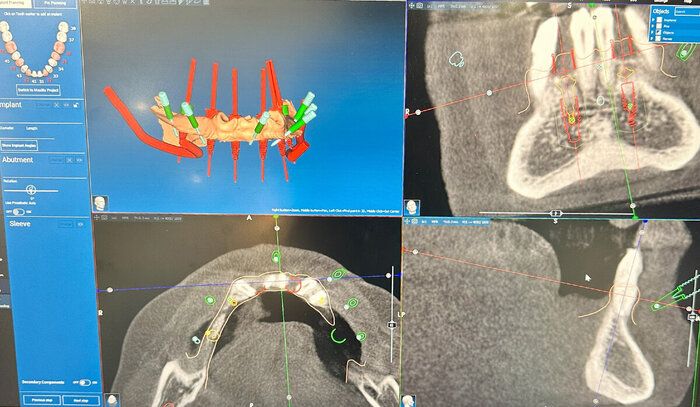

Вот как выглядит цифровая принтованная постановка:

Цифровая принтованная постановка

Разница - в первом варианте зубы не из стандартного набора, а те, что пациенту подходят больше. С этим прототипом можно даже пожить какое-то время, попривыкать к нему. Понять, что нравится, а что не особо.